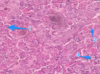

ID tissue and Specific structures labeled

Spleen

- Lymphatic Nodule

- Germinal Center

- Capsule

- Red Pulp

*keep in mind: splenic cord, venous sinus, trabecula